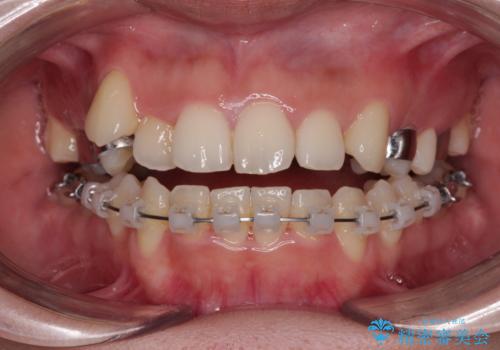

- 矯正装置

- クリアブラケット

上顎の急速拡大装置を使用して上顎骨を側方に拡大することで上顎歯列を拡大し、下顎歯列も拡大できるようにすることで、歯列を整えることとしました。

歯列矯正では基本的に骨格を改善することはできませんが、急速拡大装置(MARPE)を使用することで上顎骨を側方に拡大させることができ、咬合状態を大きく改善することができます。